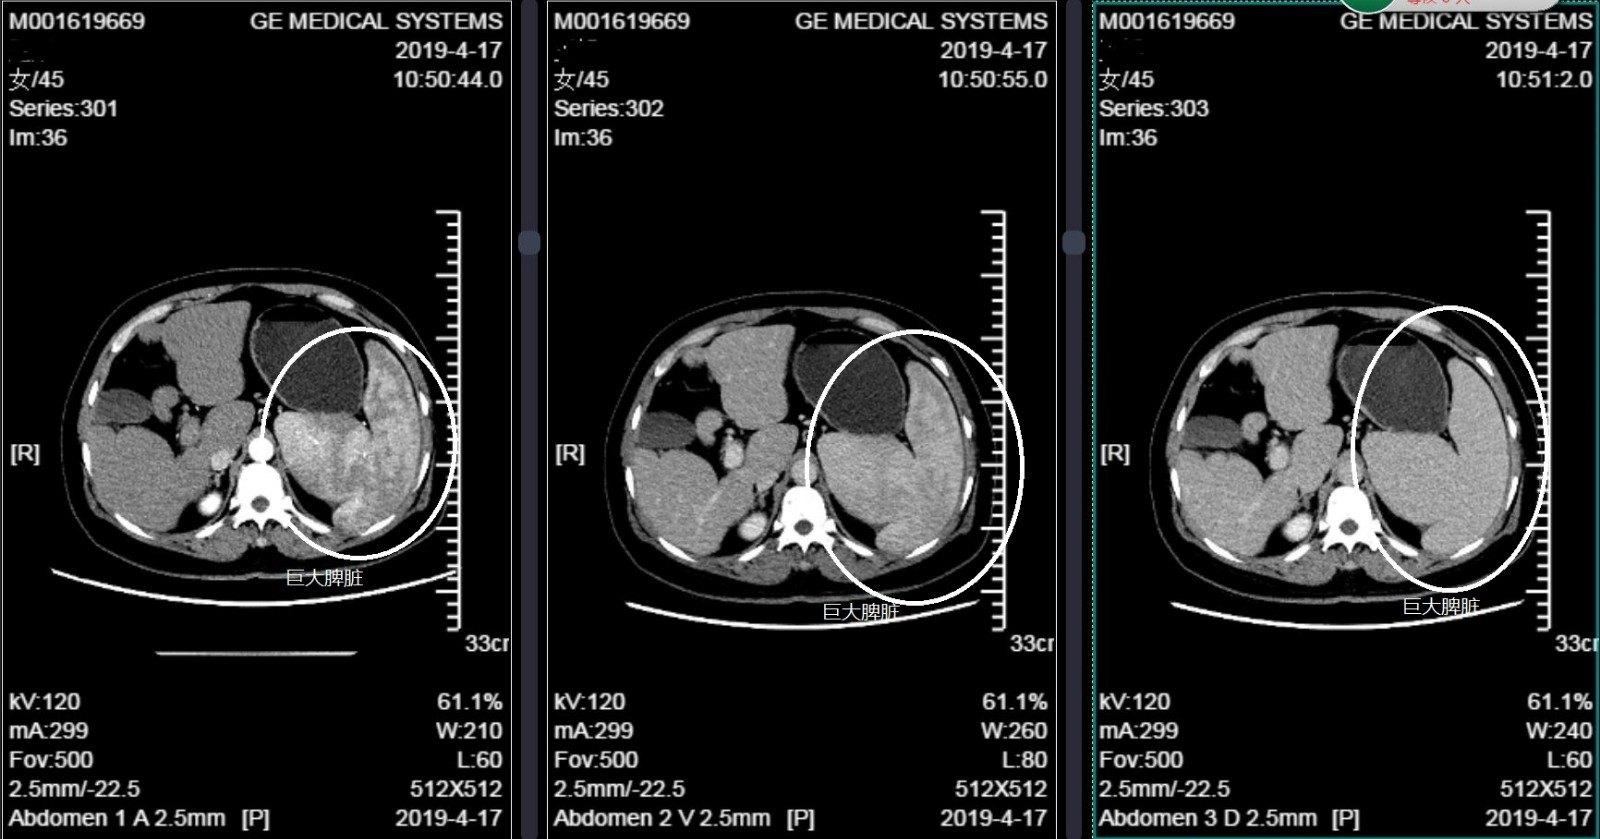

图2 术前ct显示脾脏增大

术前ct提示脾大超声刀切开胃结肠韧带游离出脾动脉并用丝线结扎,使

cl2947:巨脾(白血病)